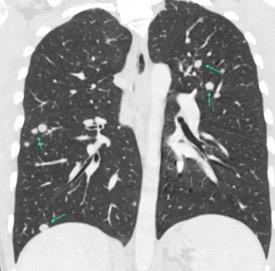

Nódulos pulmonares múltiples. (flechas verdes). Masas paratraqueales. (flechas amarillas). Dudoso ensanchamiento retrocrural (flechas negras). sigue….

Ttawfik A et al. Trans-diaphragmatic Pathologies: Anatomical Background and Spread of Disease on cross-sectional Imaging. Current Problems in Diagnostic Radiology. 2021.

T. mixto de células germinales del testículo

izquierdo Metástasis pulmonares. (flechas verdes). Ganglios paratraqueales. (flechas amarillas). Ganglios retroperitoneales (flechas negras)

Tawfik A et al. Trans-diaphragmatic Pathologies: Anatomical Background and Spread of Disease on cross-sectional Imaging. Current Problems in Diagnostic Radiology. 2021.